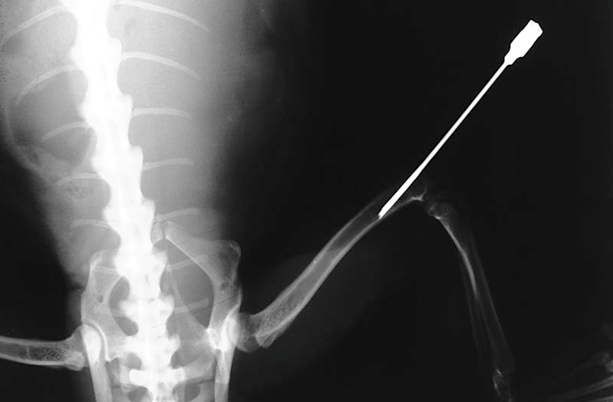

骨髄内投与(骨髄内注射)

骨髄内投与は、静脈投与よりも簡単な救命救急技術で、トカゲとカメで使用できます。一般的には、骨髄針(または非常に小型の種の場合は25g前後の注射針)を大腿骨遠位部あるいは脛骨近位部から挿入します。四肢を屈曲させ、大腿骨あるいは脛骨結節の位置を特定して可能な限りに無菌的な操作で、針を髄腔に向けます。骨髄の吸引され、ヘパリン化生理食塩水でのフラッシュに対する抵抗の低さ、またはX線撮影によって、正しい位置を確認します。代謝骨疾患を患っている個体では、四肢骨折が潜在的な合併症であるため、細心の注意を払う必要があります。大型の陸ガメでは、腹甲骨橋の髄腔に挿入できます。